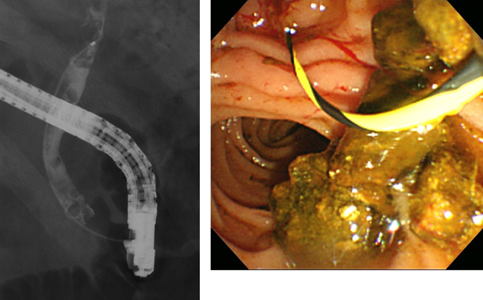

内視鏡を挿入し、十二指腸乳頭開口部から総胆管へ造影剤を流すことで結石の有無や胆管・膵管の異常を診断することが出来ます。また、総胆管結石の除去を行うことが出来ます。